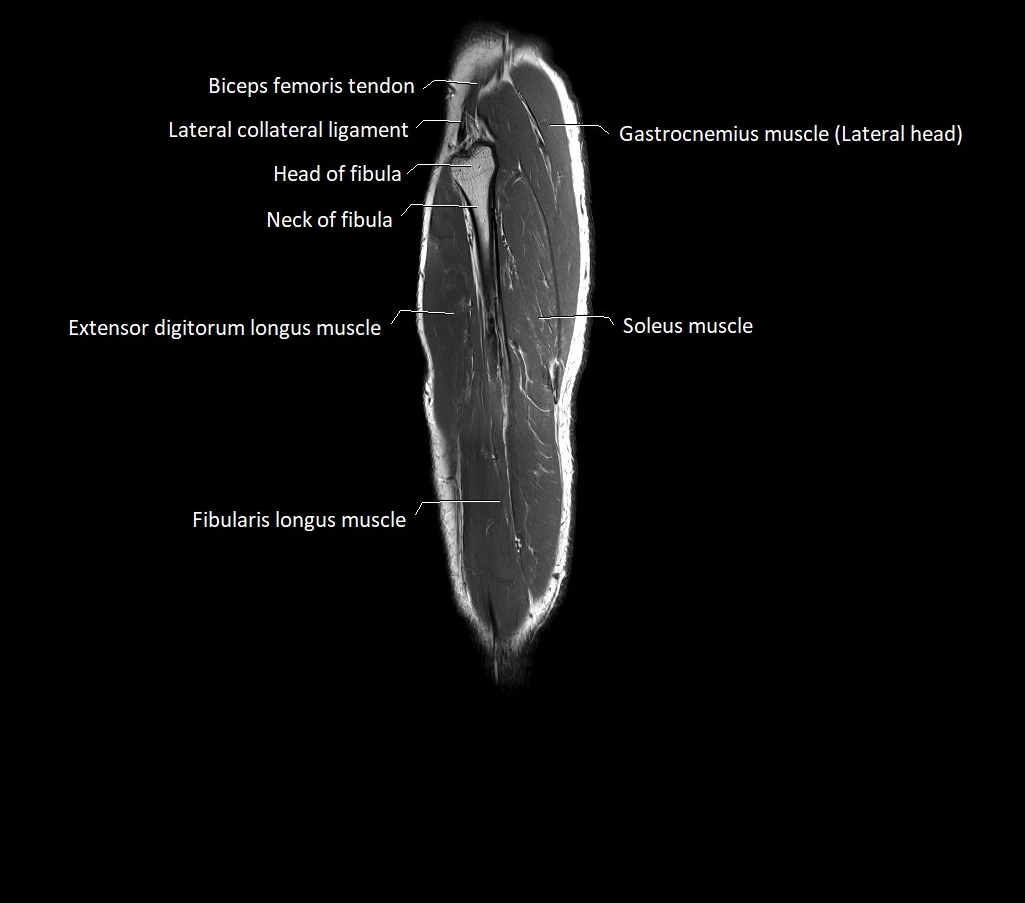

- Head of fibula

- Neck of fibula

- Lateral collateral ligament

- Extensor digitorum longus muscle

- Fibularis longus muscle (peroneus longus muscle)

- Soleus muscle

- Lateral head of gastrocnemius muscle